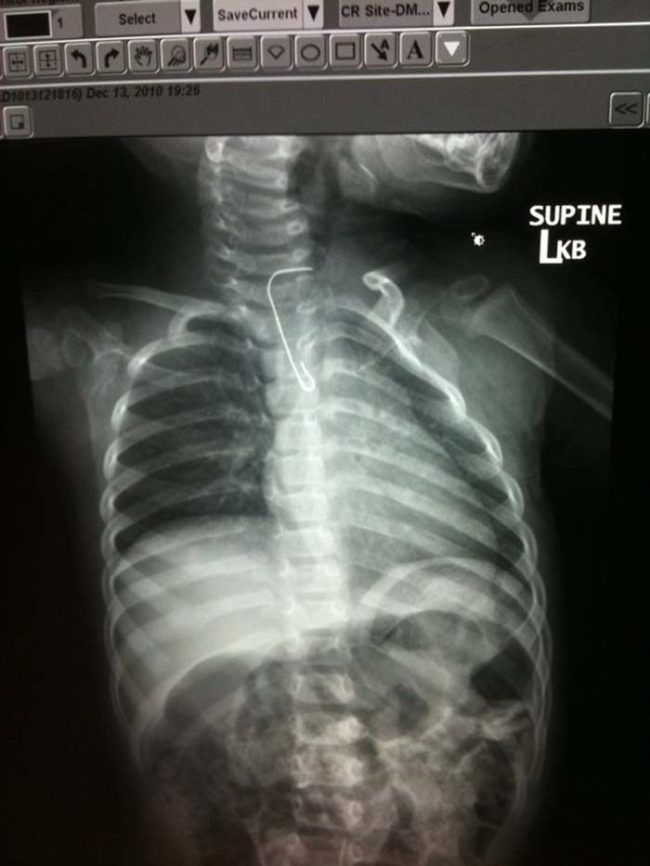

/ 8Agrafka?

I właśnie dlatego trzeba jeść powoli i dokładnie przeżuwać każdy kęs.